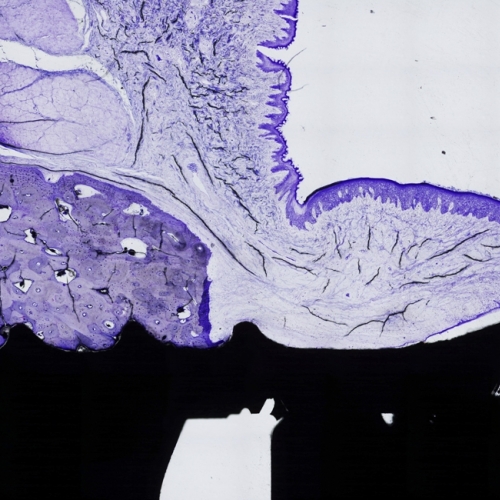

Mediante la inclusión en plástico y la técnica de lámina delgada en iBoneLab obtenemos imágenes microscópicas de alta calidad de cualquier material duro, ya sea orgánico o sintético.Más información -

Hemos optimizado la técnica histológica de “lámina delgada”, que nos permite que tanto los tejidos como los materiales implantados permanezcan inalterados para su estudio microscópico.